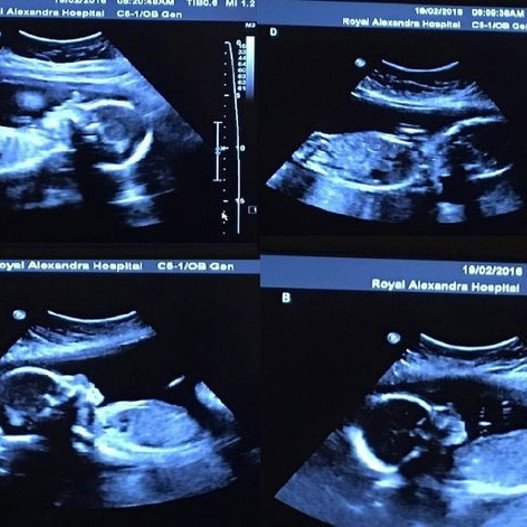

Η 22χρονη Μπέθανι και ο23χρονος Τιμ Γοέμπ από την Αλμπέρτα του Καναδά βρίσκονται μόλις λίγους μήνες από την απόκτηση αυτού που επιθυμούσαν μόνο λίγο κάπως διαφορετικά. Η 22χρονη περιμένει τετράδυμα.

Το ζευγάρι που παντρεύτηκε τον Ιούνιο και ανακάλυψε την εγκυμοσύνη τον Σεπτέμβριο, έπαθε σοκ όταν έμαθε ότι ο πελαργός θα τους φέρει τετράδυμα, κύηση για την οποία οι πιθανότητες είναι μία στις 15.000.000.

«Είμαι σίγουρα χαρούμενη που ήμουν ξαπλωμένη επειδή δεν μπορούσα να το πιστέψω ότι υπήρχαν τέσσερα μωρά εκεί. Σκεφτόμουν ότι πρέπει να είχε γίνει κάποιο λάθος. Ο άνδρας μου σχεδόν λιποθύμησε» σημειώνει η σύζυγος.